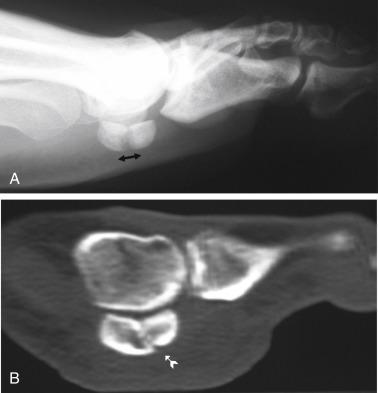

• Radiographs provide enough information to evaluate structural abnormalities in the ankle and foot, but limited information about the sesamoid bones. For a better visualization of the medial and lateral sesamoids, a medial oblique view and a lateral oblique view, respectively, can be acquired. An axial sesamoid view can provide a better assessment of both sesamoids with their metatarsal articulations and number of fragments ( Fig. 21.2 )

FIG. 21.2

• Computed tomography

• Very helpful to differentiate sesamoid acute and stress fractures from a delayed union; also useful to assess vitality of the fracture site in case of avascular necrosis. The differentiation between an acute sesamoid fracture and a bipartite sesamoid can also be achieved with a computed tomography scan. Contrary to the acute fracture with sharp edges, the bipartite sesamoid has blunt edges